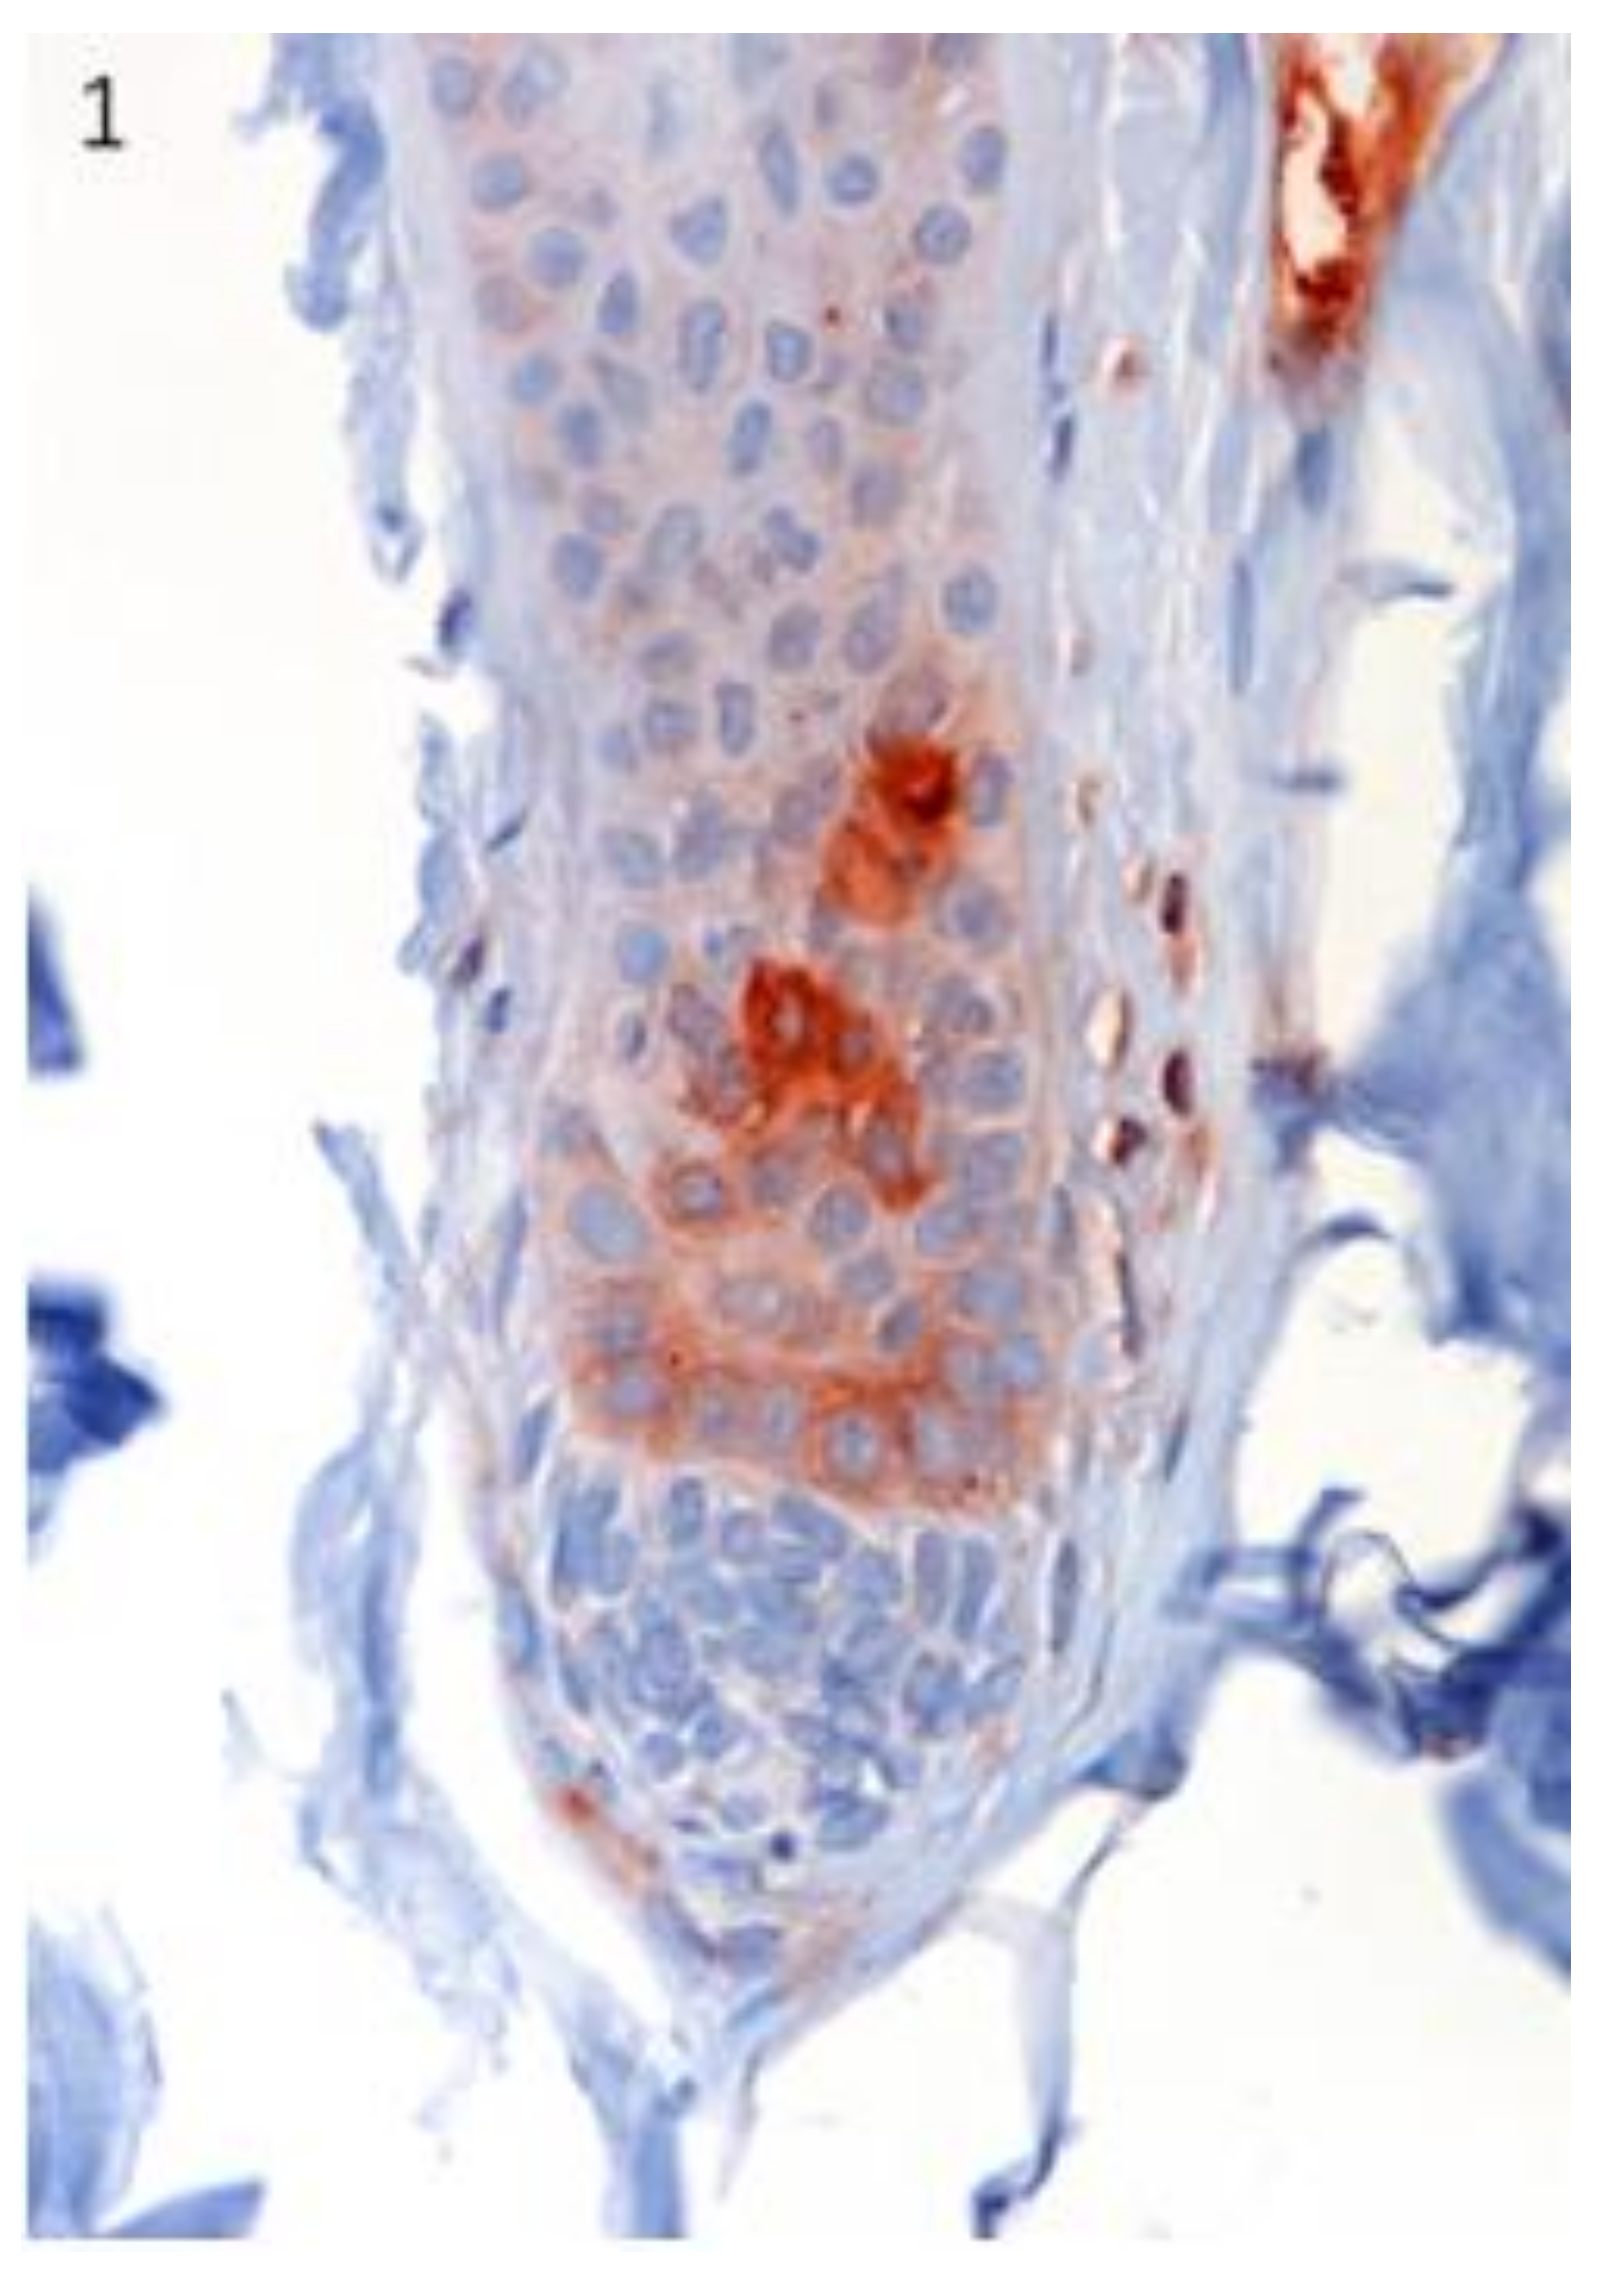

Lgr5 protein expression was immunohistochemically evident in the secondary germ of the telogen and early anagen HF (Figure 1).

Figure 1.

The localization of Lgr5 was confirmed in specific regions of canine hair follicle in healthy skin. Lgr5 protein expression was immunohistochemically evident in the secondary germ of the telogen and early anagen hair follicle (HF). Magnification 40×.